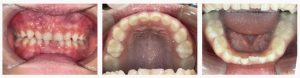

▼ Before(治療前)

マイオブレイス装着開始(機能改善トレーニング併用)

夜間と日中1時間の装着を習慣化し、装置の扱いに慣れるところからスタート。

同時に、舌のスポットポジション練習、鼻呼吸、姿勢・飲み込み方のトレーニングも行い、

歯並びを支える機能面の改善を進めました。